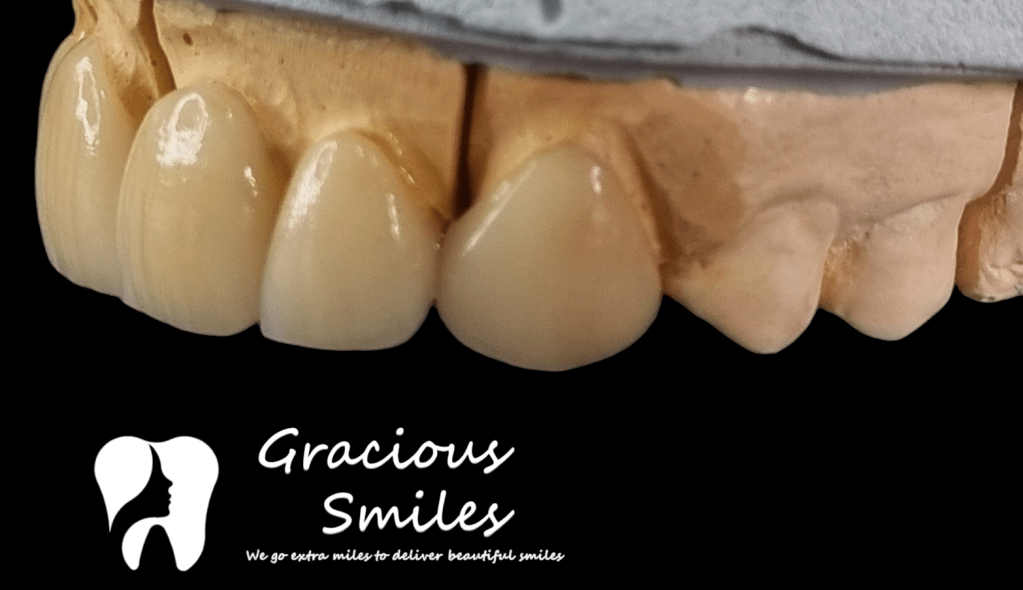

Ceramic Veneers